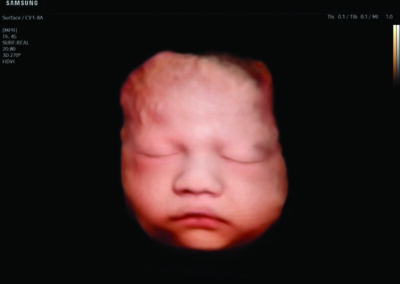

Comprehensive, advanced and expert MFM care for high-risk pregnancies